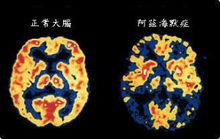

阿茲海默的父親是家鄉的一名公證人。阿茲海默先後進入柏林阿沙芬堡、蒂賓根大學和維爾茨堡大學。1887年,他在維爾茨堡大學獲得醫學學位。次年,他花了5個月時間幫助一位精神病女患者,然後進入法蘭克福市立精神病院。EmilSioli擔任精神病院院長(1852年-1922年),另一位神經科醫師尼梭(1860年-1919年)與阿茲海默共事。阿茲海默後來在腦病理學方面的許多工作使用了尼梭的組織學的銀黃著色方法。阿茲海默與人一同創辦出版雜誌 Zeitschriftfürdiegesamte Neurologieund Psychiatrie。正常與異常大腦比較1901年,阿茲海默在法蘭克福精神病院觀察了一位患者D夫人,這位51歲的患者有奇怪的行為症狀,喪失了短時記憶。在以後數年中這位患者困擾了他。1906年4月,D夫人去世,阿茲海默將病歷和腦送往他工作的慕尼黑克雷佩林實驗室。2位義大利醫生和他一起工作,他使用著色技術鑑定澱粉和神經原纖維混亂。1906年11月3日,進行了老年痴呆症首次病理學和臨床症狀演說。